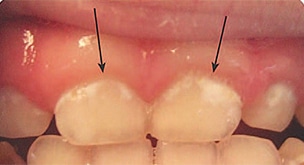

Severe ECC (S-ECC) is defined as any sign of smooth-surface caries in children younger than age 3. Additionally, in children ages 3 through 5, one or more dmf surfaces in primary maxillary anterior teeth, or a dmf score of ≥ 4 (age 3), ≥ 5 (age 4), or ≥ 6 (age 5) surfaces also constitutes S-ECC.3 The typical early sign of ECC is the crescent shaped white spot lesion at the gingival margin (Figure 1 to Figure 4).

Although not approved for caries prevention by the FDA, the American Dental Association (ADA), has recommend fluoride varnish for caries prevention in young patients who are at moderate to high risk.19 The dental community therefore, uses fluoride varnish as “off label efficacy” because of its success in community-based programs. For example, a Kentucky program that used fluoride varnish with 6,000 elementary school students reduced caries incidence from 50% to 11% over 5 years.23 In fact, varnish is used and recommended for children younger than 6.24 Using varnish on white spot lesions— the cardinal first sign of decalcification—has been an important strategy to control ECC.